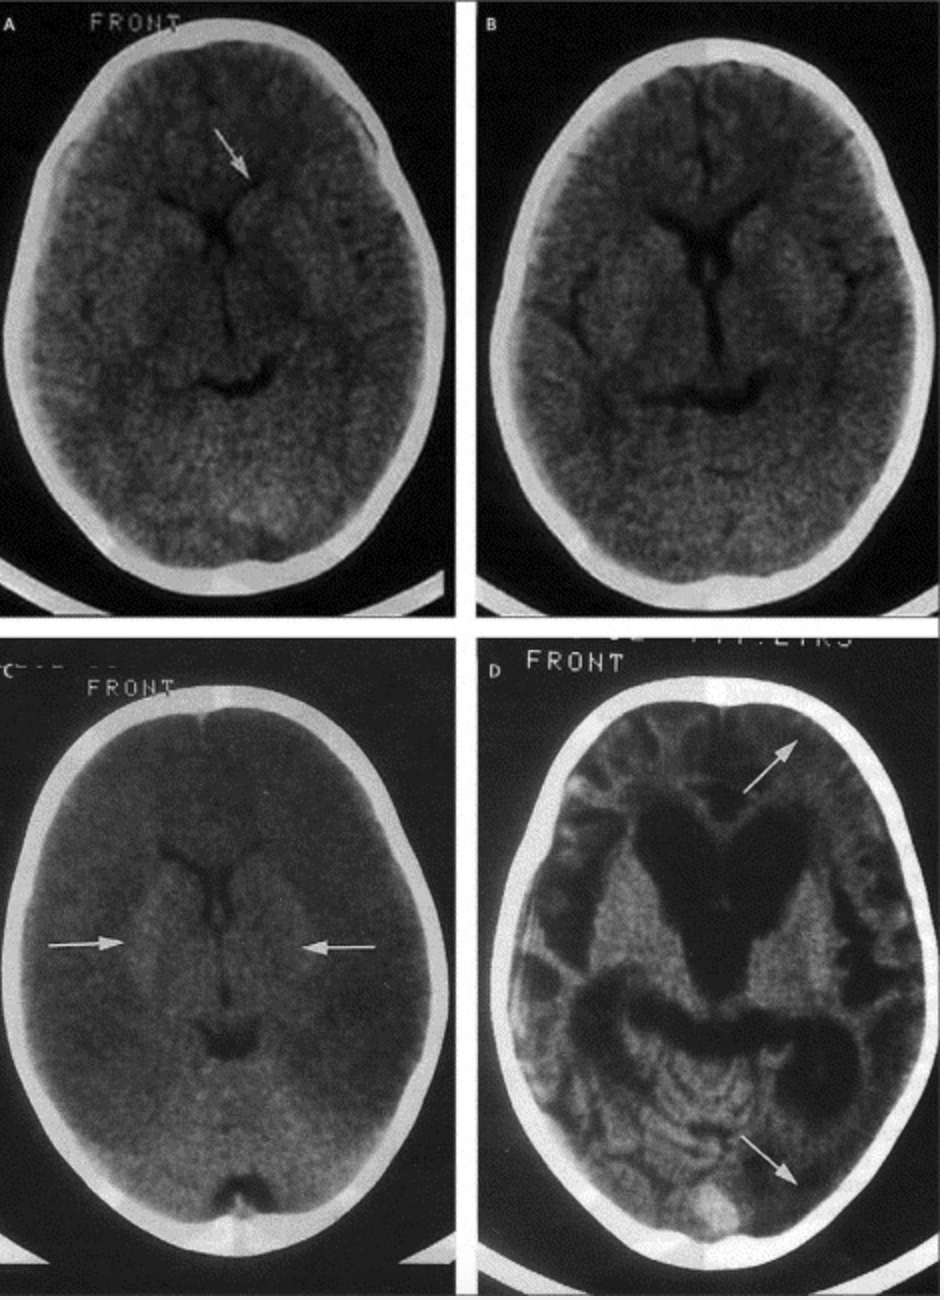

Most deadly (1 million deaths per year- anaemia and cerebral malaria)

Sequestration- parasitized RBCs: glomerulonephritis, hypoglycaemia, pulmonary edema

Hypoglycaemia (coma, convulsions)

Children: Impaired hepatic gluconeogenesis, increased glucose consumption in peripheral tissues and by parasites, normal insulin levels

Adults: Hyperinsulinemia due to parasite stimulation of pancreatic islet cells or quinine/quinidine therapy

| Impaired consciousness | Glasgow coma score <11 in adults or Blantyre coma score <3 in children; inability to swallow |